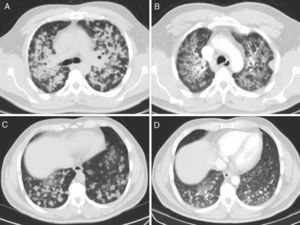

Our patient was a 49-year-old man, originally from Ecuador, non-smoker, with no significant personal history and no known contact with patients with active tuberculosis. He consulted due to a 10-month history of chronic productive cough, mucopurulent, occasionally with bloody sputum, in addition to intense hyporexia and a 3kg weight loss. Chest X-ray showed bilateral pulmonary infiltrates with some poorly defined, pseudonodular images, predominantly in the upper lobes. He was hospitalized in a respiratory isolation room with an initial suspicion of tuberculosis, but sputum smears were negative. After multiple bilateral pulmonary nodular opacities, mostly cavitary, were seen on the chest computed tomography (CT) (Fig. 1A and C), a thorough, bilateral bronchoscopy was performed that showed no pathological findings. A cytological study of the bronchoalveolar lavage samples was conducted, yielding a diagnosis of lung adenocarcinoma with micropapillary pattern. The exon 19 deletion was positive, while the rest of the mutations studied were negative (L858R, T790M, G719A/C/S, exon 20, S768I and L861Q, ALK and ROS1). The patient began treatment with gefitinib, with a good clinical and radiological response at 4 months (Fig. 1 B and D).

Our case is unusual due to the uncommon radiological presentation. Accordingly, we believe that lung adenocarcinoma should be included in the differential diagnosis of this radiological pattern.